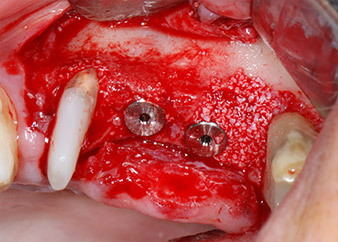

implants prêts à recevoir les vis de couverture

Fig. 12 : Les deux implants sont en place et prêts à recevoir les vis de couverture.